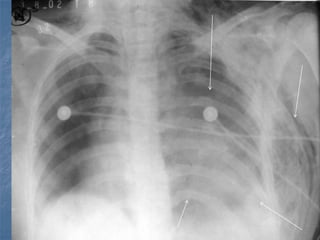

TÓRAX INESTABLE

Fractura de 2 o más costillas en dos o

más lugares con pérdida del soporte

óseo de un segmento del tórax.

Contusión pulmonar y dolor, respiración

superficial, respiración paradójica,

crepitación ósea, enfisema subcutáneo.

Radiografía de tórax.